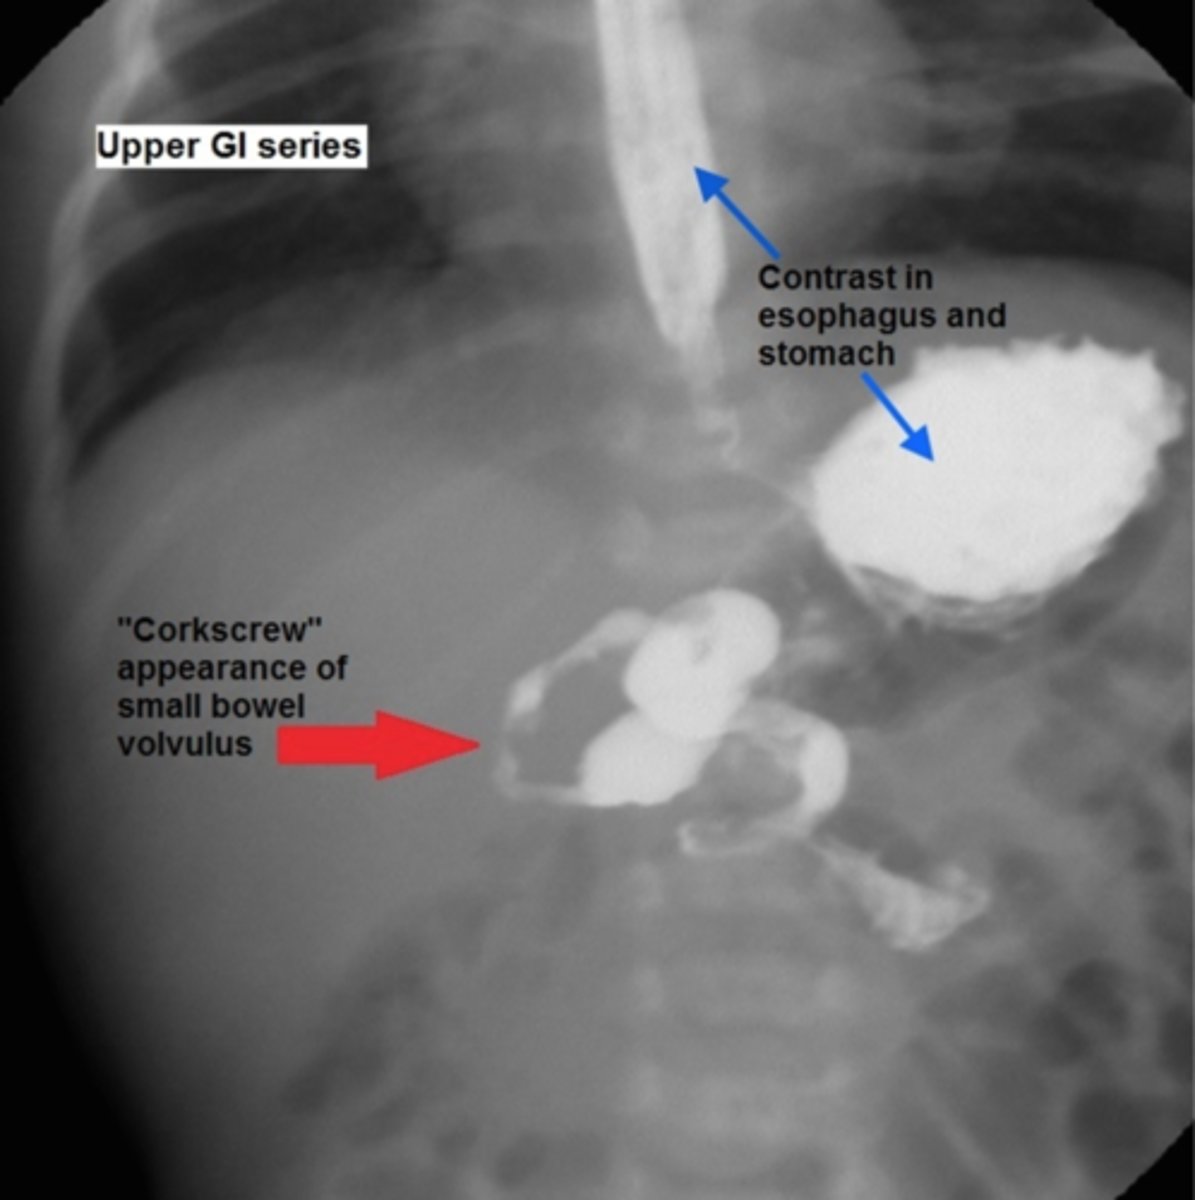

What is the best initial diagnostic test for suspected malrotation/midgut volvulus, & what must this be followed up by? What will be seen?

Initial: abdominal x-ray - double bubble sign and/or air-fluid levels (remember need to d/dx duodenal atresia from this)

Best: upper GI contrast series/contrast enema - twists of barium w/ bowel pushed over to the right